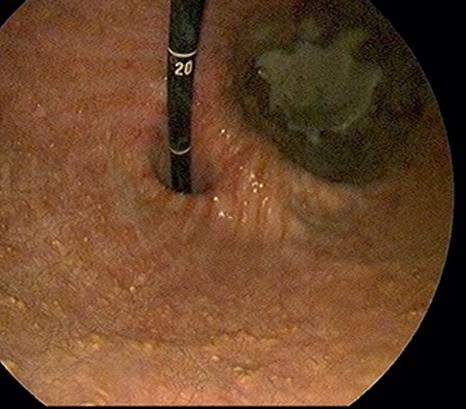

Diagnosis relies on visualisation of ulcers in the stomach region, and this is achieved with the use of a Gastroscope.

The apparatus is a three-metre-long flexible tube that is passed down the oesophagus via the nostril.

Acamera on the end of the scope is used to view the inside of the stomach, with the Gastroscope being connected to a computer screen.

AGastroscope gives us the ability to view the squamous, glandular and pyloric regions

of the stomach - all common areas for ulcers. During your horse’s scope, the vet can take video or photos of any area of interest. Prior to scoping, your horse's stomach will need to be empty, therefore fasting is carried out from the previous evening.

Asedative is used to help keep your horse relaxed and comfortable - the procedure is not painful but it can be a little unfamiliar for your horse.

Diagnosis of ulcers in the stomach region is achieved with the use of a Gastroscope.

AGastroscope examination of your horse’s stomach can provide quick information for treatment of gastric ulcers.